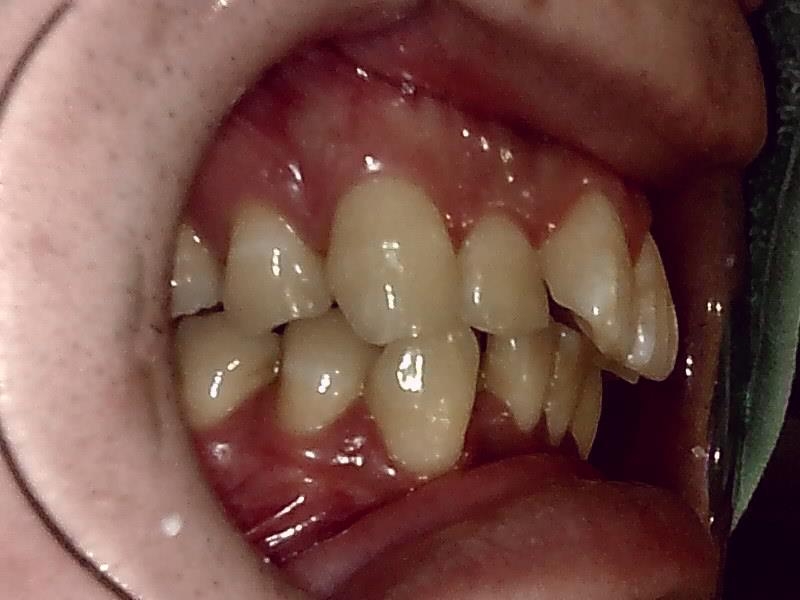

右側

スマイルラインも美しくなり、前突した歯も改善され噛み合わせもしっかり正常に戻しました。

術後 リテーナー保定装置で保定します。